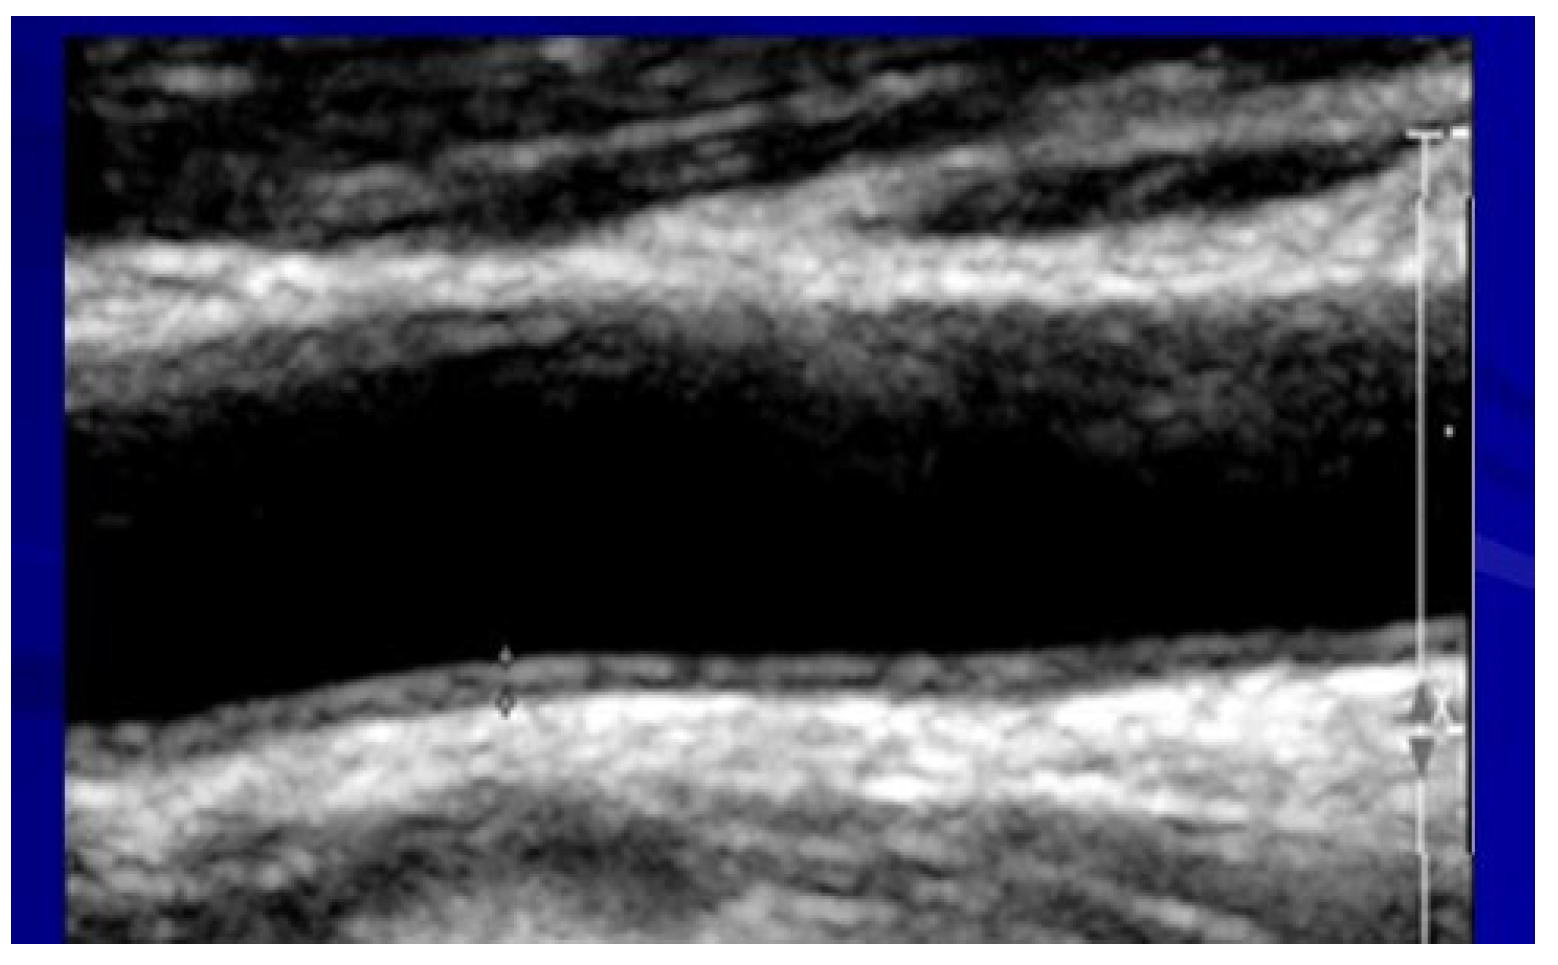

2.5. Assessment of Carotid Atherosclerosis

| IMT * | 0.86 ± 0.1 | 0.98 ± 0.3 | 0.83 ± 0.1 | 0.01 |